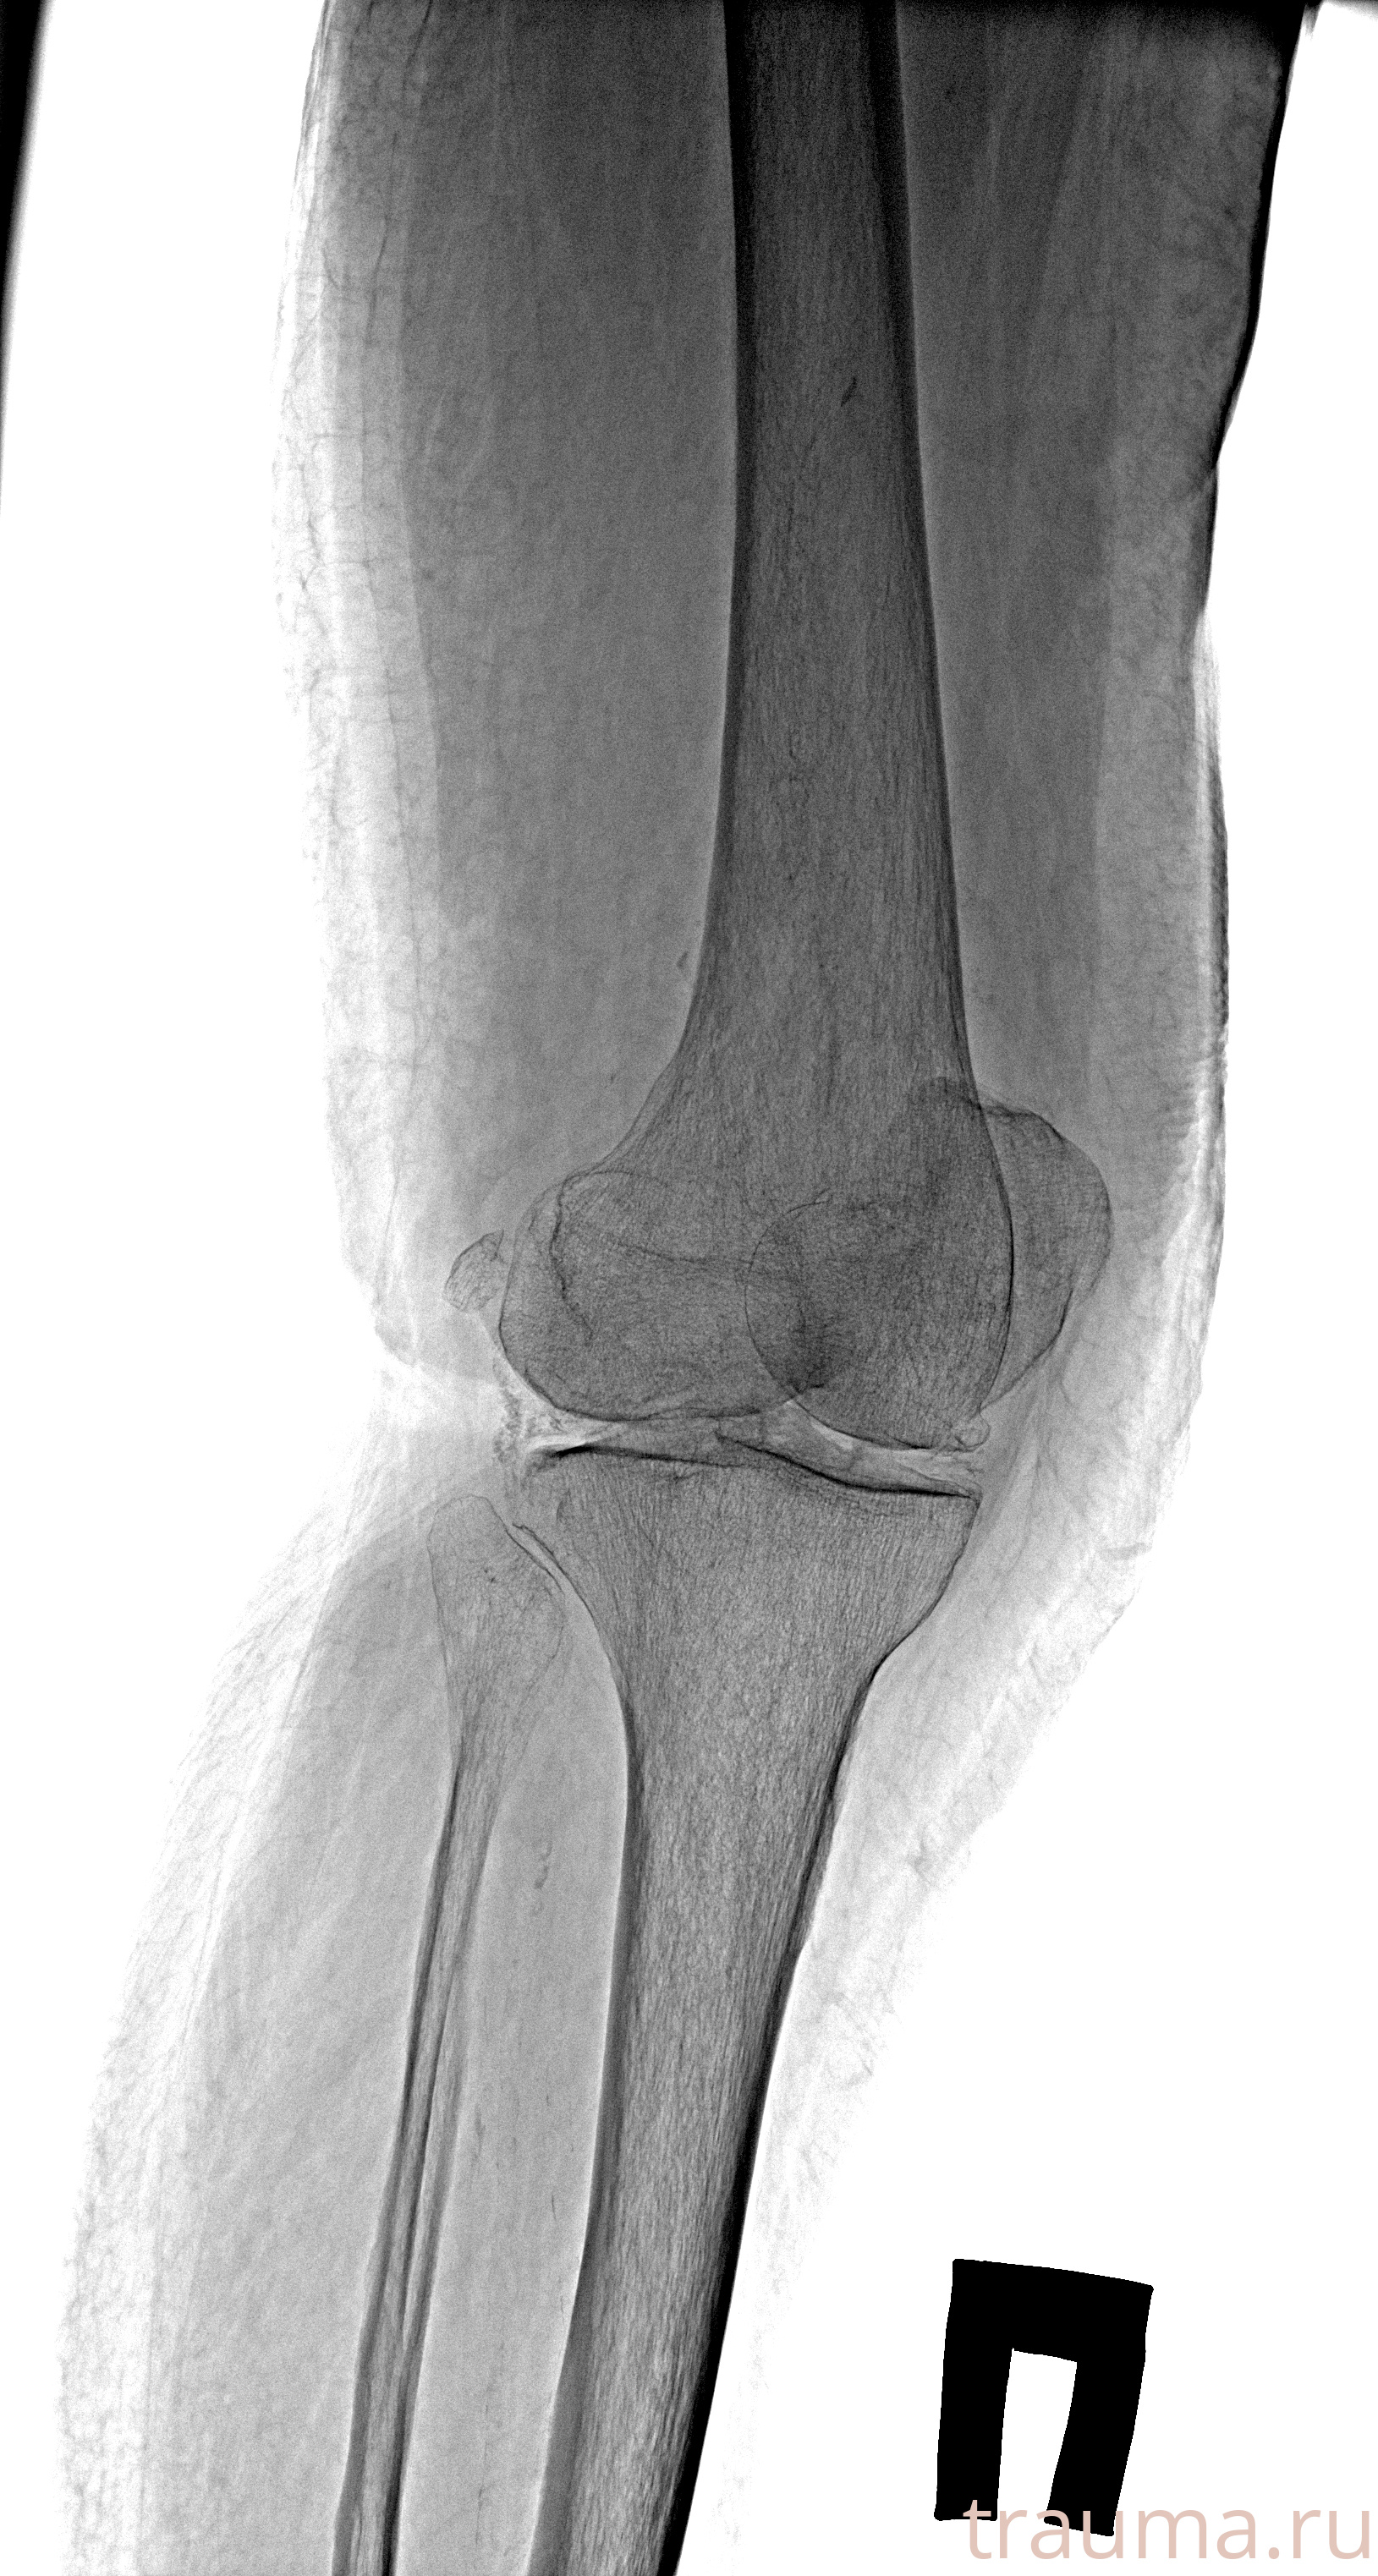

Рентгенограммы

Рентген на дому: по вашему адресу приезжает врач-рентгенолог, травматолог-ортопед с мобильным рентгеновским аппаратом, проводит диагностику травмы или заболевания, делает необходимые рентгенограммы, дает рекомендации по дальнейшему лечению. Получить качественные снимки в домашних условиях возможно благодаря уникальной методике, разработанной МосРентген Центром для института  Склифосовского